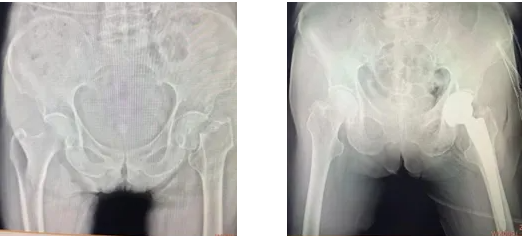

患者术前、术后X线对比

在手术团队、麻醉科及手术室的精密配合下,手术历时约一小时顺利完成。术后X光片显示假体位置精准,效果理想。